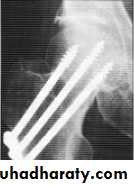

Type 1 & 2 : they are already reduced just do closed internal fixation.

Type 3 & 4: closed reduction + internal fixation if faileda- age <60 years ORIF

b- age >60 years partial hip replacement (Austin moore)